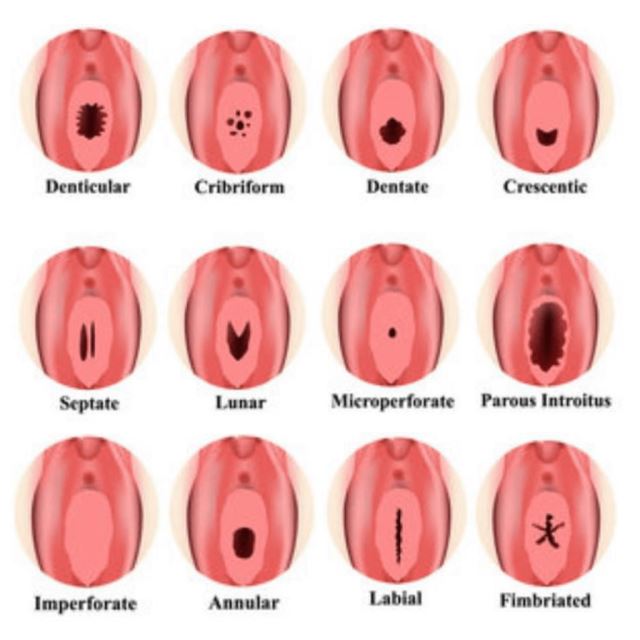

پردهی بکارت یک بافت گوشتی نازک است که در ابتدای ورودی واژن زن قرار دارد. این ورودی شکلهای مختلفی دارد و در بیش از نیمی از خانمها بعد از برقراری رابطهی جنسی و یا ورود یک جسم خارجی به داخل واژن پاره میشود و با یا بدون خونریزی این پارگی را نشان میدهد. از آن جایی که مسئلهی باکرگی در فرهنگها و مذهبهای مختلف تعاریف متنوعی دارد و از نقطهنظرهای مختلفی به این مسئله نگاه میشود، برخی از افرادی که علارغم باورها و اعتقادات مذهبی و عرفیشان، رابطهی جنسی داشتهاند و دچار پارگی پردهی بکارت شدهاند، با مشکل مواجه شدهاند و به ترمیم پردهی بکارت فکر میکنند.

در این حالت ممکن است فرد دچار درد یا خونریزی شود. با توجه به انواع مختلف مدل های غشایی ظروف، آسیب های ناشی از آن نیز می تواند انواع مختلفی داشته باشد.